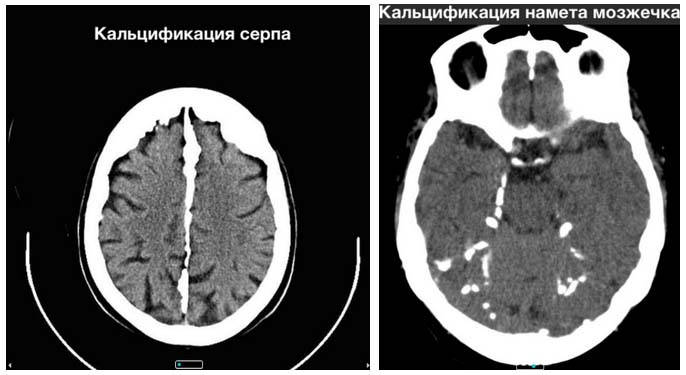

Физиологическая кальцификация чаще всего наблюдается в структурах головного мозга, известного как «мозговой песок». Наиболее распространенным является обызвествление шишковидной железы, которое у большинства людей к 30 годам уже хорошо визуализируется при обследовании. Также часто встречается физиологическое обызвествление в базальных ганглиях, твердой оболочке мозга, серпе, наметке мозжечка, каменисто-клиновидной связке, сосудистом сплетении боковых желудочков, зубчатых ядрах мозжечка и верхнем сагиттальном синусе.